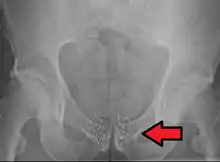

Som eksempler på kræftformer, der ofte behandles med brachyterapi, kan nævnes livmoderhalskræft og prostatakræft.